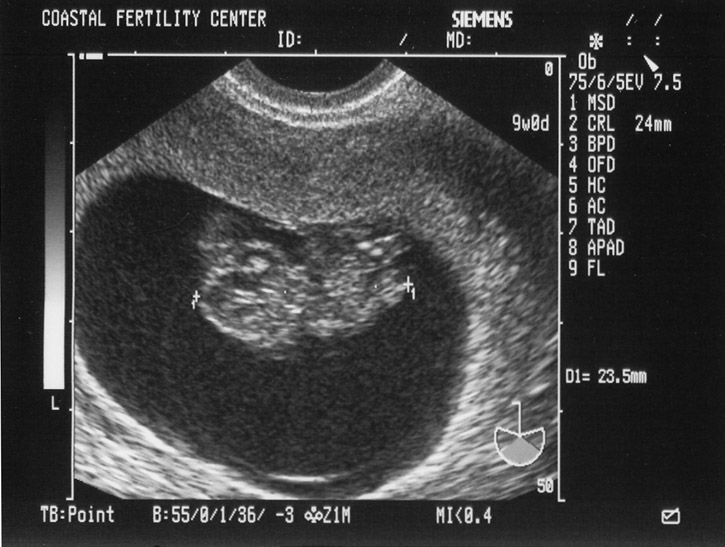

5/17/05 Baby A - 9w0d